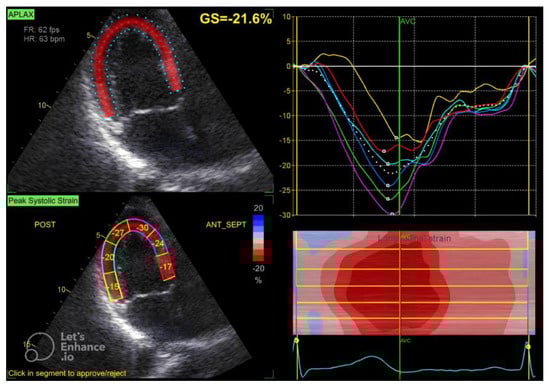

2.2. Echocardiographic Assessment

| GLS (%) | −20.25 ± 2.53 |